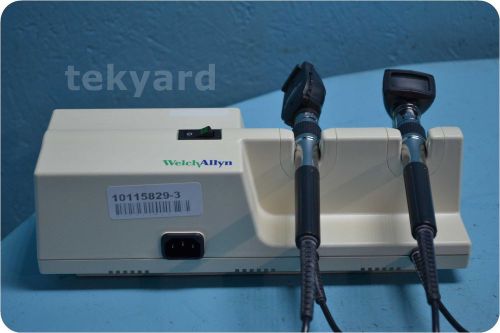

WELCH ALLYN 767 OTOSCOPE / OPHTHALMOSCOPE WALL MOUNT TRANSFORMER (WITH HEADS) *

WELCH ALLYN 71100 OTOSCOPE OPHTHALMOSCOPE + BASE CHARGER STATION